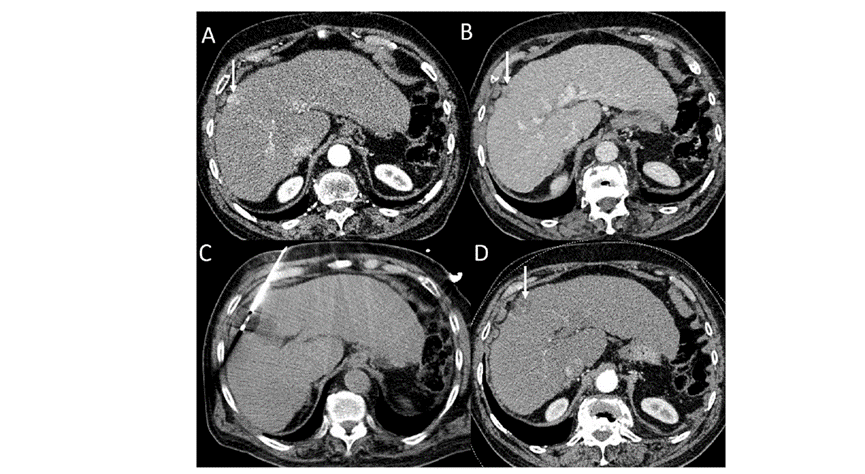

(A)動脈期CT圖像顯示有一個包膜下結節(箭頭)。(C) 在手術過程中的CT顯示一個冷凍探針位于病灶內。隨訪時間中位數為7個月(范圍:3-12個月),隨訪期間患者無局部腫瘤進展或死亡。

(A)門靜脈期 CT 圖像顯示膽囊附近有病變(箭頭)。(D)消融手術后 1 個月CT 顯示完全消融。

本研究中患者隨訪期間無局部腫瘤進展,無死亡病例,沒有發現與手術相關的并發癥。證實冷凍消融是一種有效的治療方式,在技術上是可行和安全的。由于肝包膜下病變位置特殊,射頻消融有出血及腫瘤種植的風險,可能會對鄰近器官造成損傷,并且增加局部腫瘤進展的風險。近年來,冷凍消融術的應用逐漸廣泛,有研究顯示冷凍消融治療具有明顯優勢,可治療特殊部位的肝腫瘤。本研究的目的是評價冷凍消融治療肝包膜下腫瘤的安全性和有效性。回顧性納入2016年7月1日至2018年9月1日期間冷凍消融的57例患者。包括42例男性和15例女性,平均年齡為62.4歲(范圍:48-82歲)。每個患者有1個或2個平均腫瘤尺寸為2.4cm的病變(范圍:0.6-4.0cm)。所有患者均患有慢性肝病或肝硬化,并伴有乙型肝炎(n=52)、丙型肝炎(n=3)和其他肝炎(n=2)。根據腫瘤位置,在膈肌或肝臟下附近有18個病變(26.5%),胃或腸附近有9個病變(13.2%),腹壁附近有33個病變(48.5%),腎臟附近有8個病變(11.8%)。